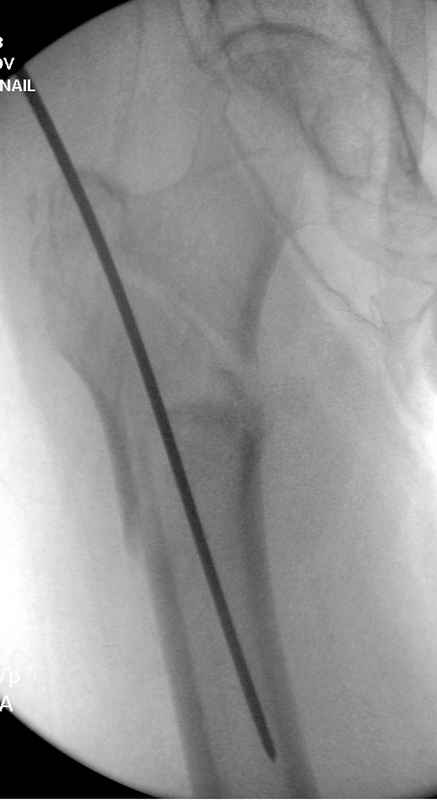

[Ortho] Чрезвертельный перелом бедра

Здесь 83 года, травма в результате падения

Вложение не в текстовом формате было извлечено…

Имя     : #5 IT fx  2introp.jpg

Тип     : image/jpeg

Размер  : 19563 байтов

Описание: отсутствует

Url     : http://weborto.net:8080/pipermail/ortho/attachments/20090826/208099a1/attachment-0008.jpg